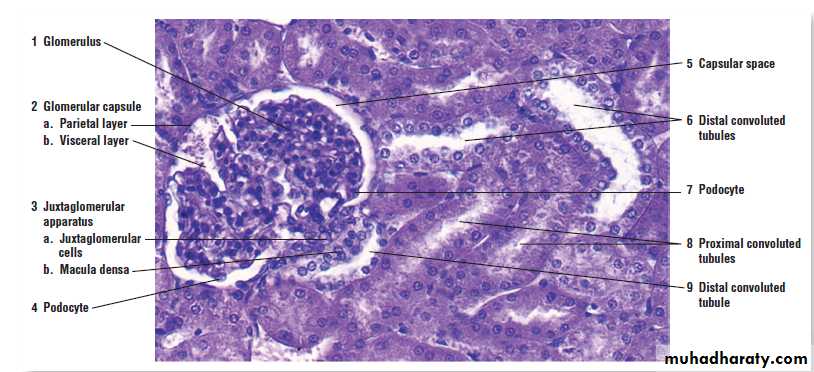

Renal Corpuscle

Renal Cortex Proximal and distal convoluted tubule

Juxtaglomerular Apparatus (JGA)